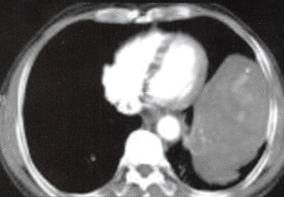

图1胸膜孤立性纤维瘤

A

B

C

D

A.B.CT平扫示左中下胸巨大肿块,宽基底与胸壁相连,内见斑片状钙化;

C~F.CT增强扫描肿块内缘肺门侧见一血管蒂样结构与纵隔相连,中度不均匀强化,内见匍行、紊乱的血管影,肿块中度均匀强化;